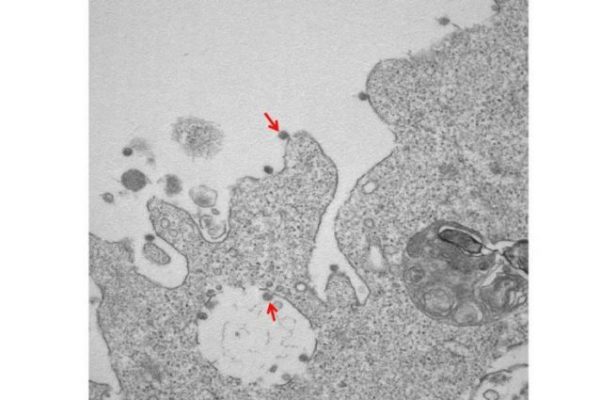

Il SarsCoV2 ha finalmente un'immagine, il virus che sta spaventando l'intero mondo ed è stato isolato in Italia. Infatti secondo...